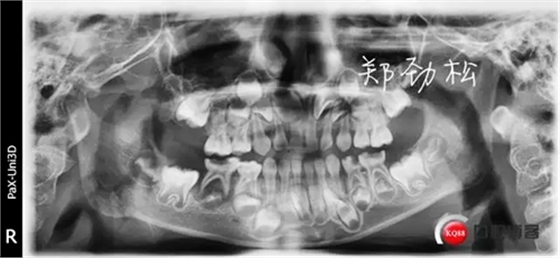

我的病例三 7E牙髓炎

836605.jpg

297418.jpg